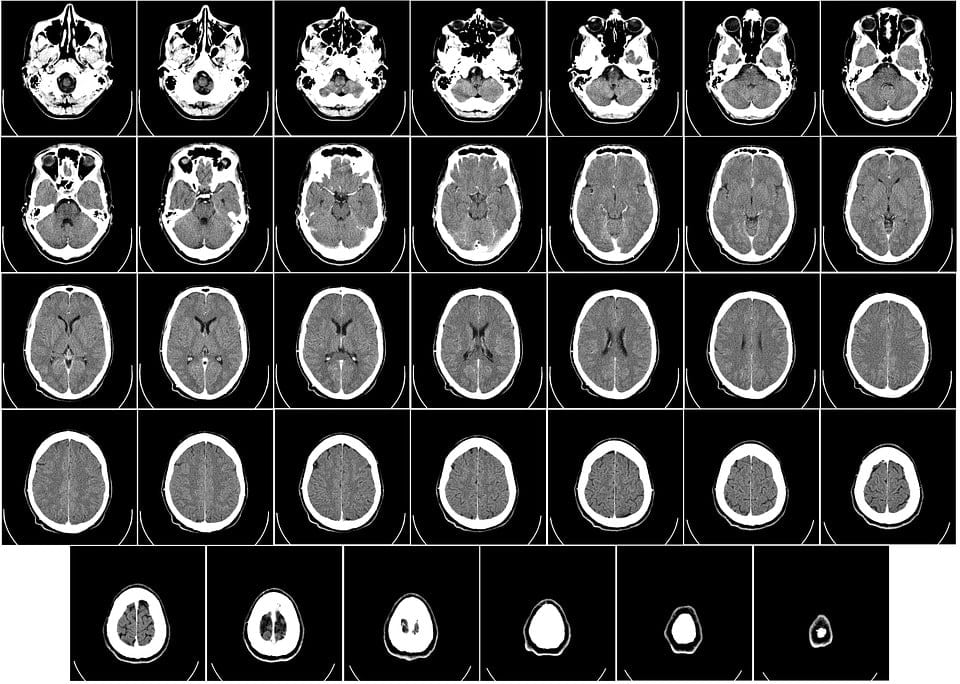

En casos un poco más complicados se puede realizar pruebas diagnósticas como encefalogramas o TACs.